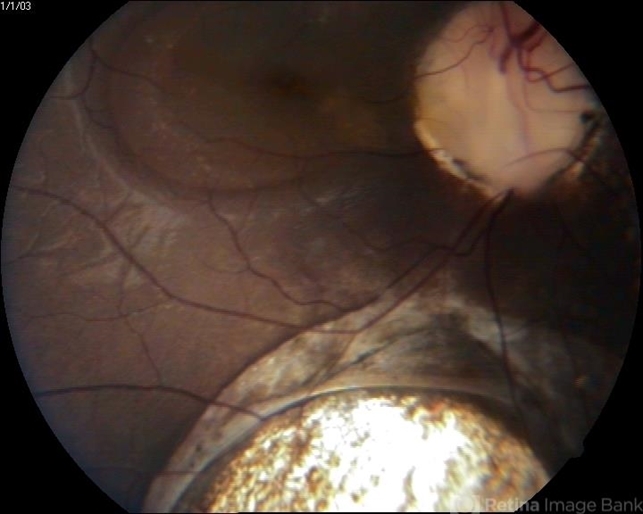

- choroidal coloboma

- 10-year-old female patient presented with loss of vision.